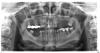

lurdes Опубликовано 24 ноября, 2008 Автор Поделиться Опубликовано 24 ноября, 2008 интересно просто....выходит те, кому тогда, в былые позавчерашние времена ставили мост 3-8.. у них всех и быстро сложилась тяжёлая стоматологическая судьба. т.е 12 лет с ним явно никто не отходил, (как я со своим 5-8..)а ещё и потерял крепёжные зубы..? Странно мне. Странно почему сегодня_никто_ из тех докторов которым я показывала свой рот (их немало) не остановил меня от установки такой конструкции! не предупредил что год,два иусё...не предложил съёмные на худой конец...Они безумные что ли,или просто мне надо поднять тему каких либо гарантий тут оно всё и выяснится... пытаюсь повесить СНИМОК. Должны быть видны и те живые зубы которые 12 лет сидят под коронками... ...ну и те пустоты которые хотят моста 3-8 или имплантации.... Жду Ваших мнений уважаемые специалисты. http://s49.radikal.ru/i126/0811/ef/81e3209709d3.jpg Ссылка на комментарий

Снежана Опубликовано 24 ноября, 2008 Поделиться Опубликовано 24 ноября, 2008 нет, ну какой мост 3 - 8, это не серьезно, там атрофия костной ткани на полкорня у клыка и восьмерка с наклоном немаленьким, вы сами посмотрите, а справа мост 6 - 8, а не 5-8. Ссылка на комментарий

lurdes Опубликовано 24 ноября, 2008 Автор Поделиться Опубликовано 24 ноября, 2008 нет, ну какой мост 3 - 8, это не серьезно, там атрофия костной ткани на полкорня у клыка и восьмерка с наклоном немаленьким, вы сами посмотрите, а справа мост 6 - 8, а не 5-8. ......т.е держаться такой мост не будет, 3 и 8-ку потеряю через пару лет. Так? Выход? Вообще то у меня зуб 5-ка - тоже часть моста ,хотя да и ладно...меня больше интересовало проверить состояние живых 6,8.. Ссылка на комментарий